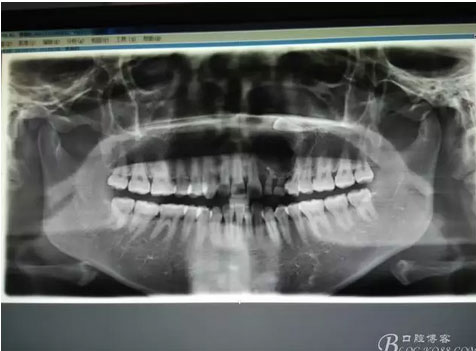

圖1。術(shù)前的CBCT影像檢查:22位于鼻底下方,23位于24、25的根方。左側(cè)乳Ⅱ、Ⅲ根方顯示囊性改變,囊腔內(nèi)大量致密鈣化團(tuán)塊,密度高。

圖21.術(shù)中拍全景片,看是否有牙瘤殘留,發(fā)現(xiàn)左側(cè)乳Ⅱ根尖區(qū)還有少量致密鈣化物,建議拔除左側(cè)乳Ⅱ、,患者要求保留兩個(gè)乳牙。經(jīng)協(xié)商,遺留極少量鈣化物,不影響整體愈合。通過骨腔探查,發(fā)現(xiàn)左側(cè)乳Ⅱ、Ⅲ根尖區(qū)未破壞,骨壁尚完整。同意遺留部分鈣化物。有點(diǎn)缺憾,為了保留乳牙和患者的美觀及功能。定期觀察遺留部分的發(fā)展變化